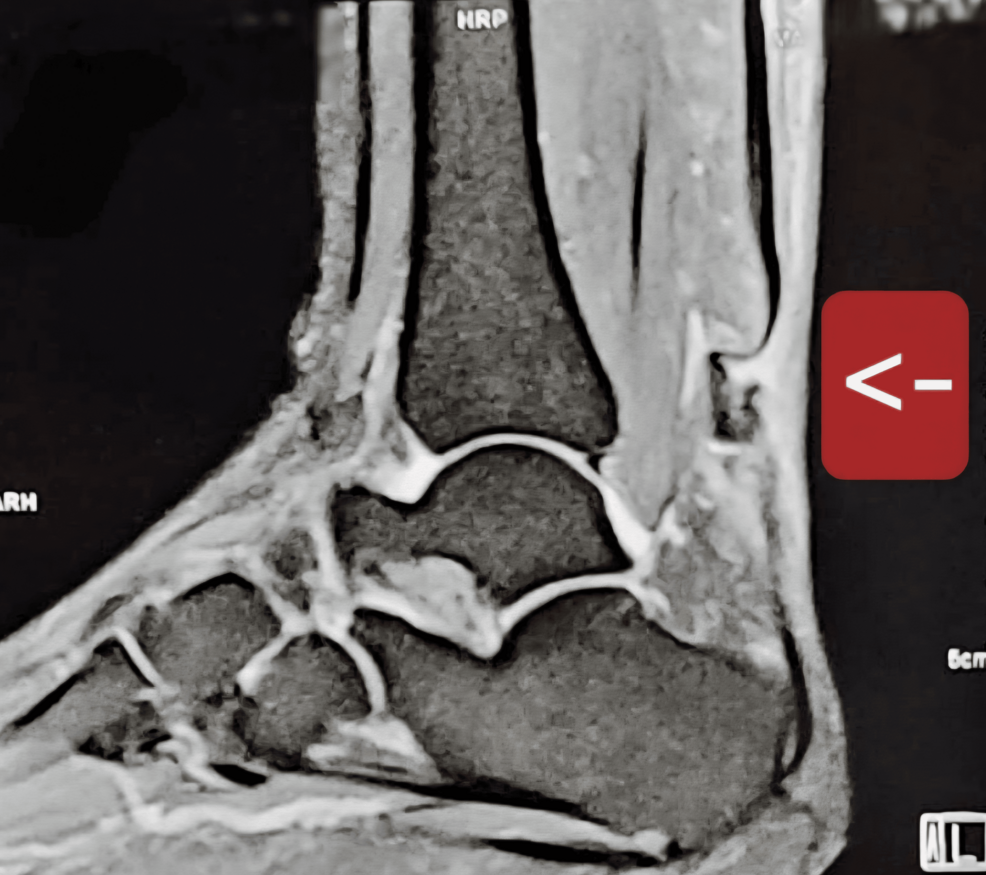

Restoring mobility after a severe tendon injury is often a grueling process, but for one patient facing the rare challenge of a bilateral simultaneous chronic Achilles tendon rupture, a combination of traditional and minimally invasive surgery provided a path back to walking. The case highlights a sophisticated surgical approach using the transfer of the flexor hallucis longus (FHL) tendon to replace the function of the Achilles, which is the strongest tendon in the human body.

The Achilles tendon is critical for plantar flexion—the action of pointing the foot downward—which allows a person to push off the ground while walking or running. When this tendon ruptures and remains untreated for an extended period, it becomes a “chronic” rupture. In such cases, the tendon ends often retract and atrophy, making a simple primary repair impossible because there is no longer enough healthy tissue to sew back together.

This specific medical case involved a patient who suffered from these ruptures in both legs simultaneously. Because the injuries were chronic, surgeons had to look beyond standard repair techniques, opting instead for a bilateral simultaneous chronic Achilles tendon rupture treated with open and endoscopic flexor hallucis longus tendon transfer. This procedure essentially “borrows” a nearby tendon to do the job of the damaged Achilles.

The flexor hallucis longus (FHL) is the muscle and tendon responsible for flexing the big toe. While essential for balance, it is not as critical for walking as the Achilles. In a tendon transfer, the FHL is rerouted from its original path and attached to the calcaneus (heel bone), effectively taking over the role of the missing Achilles tendon.

In this patient’s case, the surgical team employed a dual approach. On one side, an open surgical technique was used, providing the surgeon with a direct view of the anatomy to ensure secure fixation. On the other, an endoscopic approach was utilized. Endoscopic surgery involves using a small camera and specialized tools through tiny incisions, which typically results in less tissue trauma, reduced postoperative pain, and a lower risk of infection.